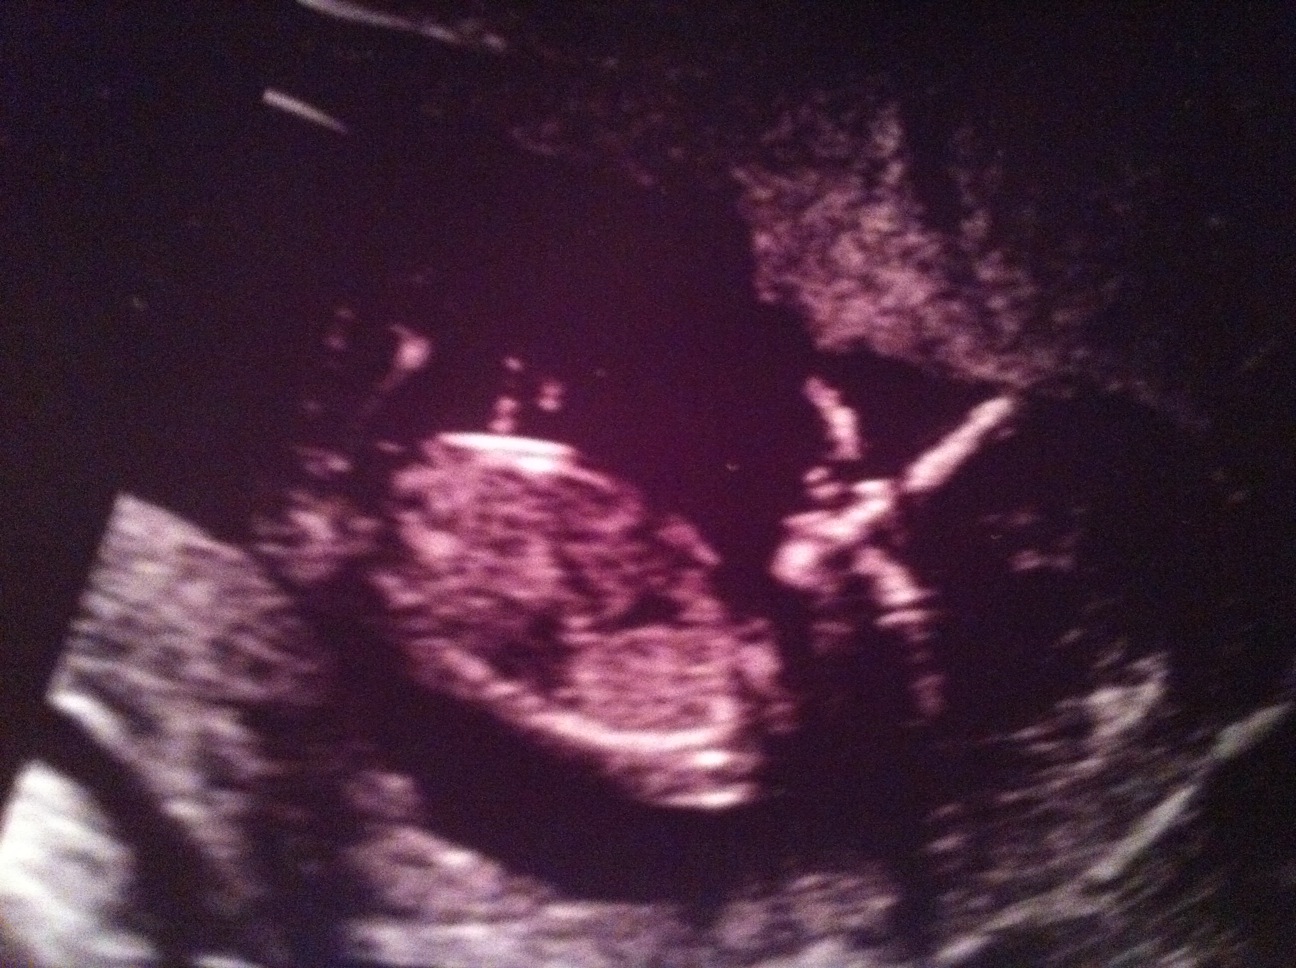

Here is a pic of the baby at 12 weeks:

I went for my NT scan a couple days ago and everything looked great! I got to see the baby bounce around the screen for almost an hour. He/she was not very cooperative and it took the tech forever to get a measurement. I could see it's little legs kicking and arms waving around. A few times it would even suck it's thumb. I'm also pretty sure that the baby is going to love the camera because it kept turning towards us everytime the tech would try and take the measurement. Then by the end of the appointment it must have had enough because it kept turning and mooning us, lol. I asked the doctor if he could make a prediction on the gender but again the baby was not cooperating. First it's legs were crossed and then the umbilical cord was in the way. We were just about to give up when we finally got a clear view. Unfortunately the little wiggle worm was moving around so much that the doctor was having a hard time judging the angle of the dangle. At first he said that if he had to guess that it was a girl but then a second later said he thought boy. The tech then chipped in that she also thought it was a boy. The doctor said the baby was moving around too much to get an accurate answer so not to buy anything pink or blue. The most important thing though is that all the measurements came back awesome. Chances of downs syndrome is 1 in 5,000 and chances of any other chromosomal diseases is 1 in 10,000! Woo Hoo!!!!! The baby was also measuring a head of schedule which moved my due date to January 4th now. The doctor said it's common for the due date to move around as long as it stays within the week. I'm going to stick with the 6th though since it seems to be in the middle of the doctor's estimate.